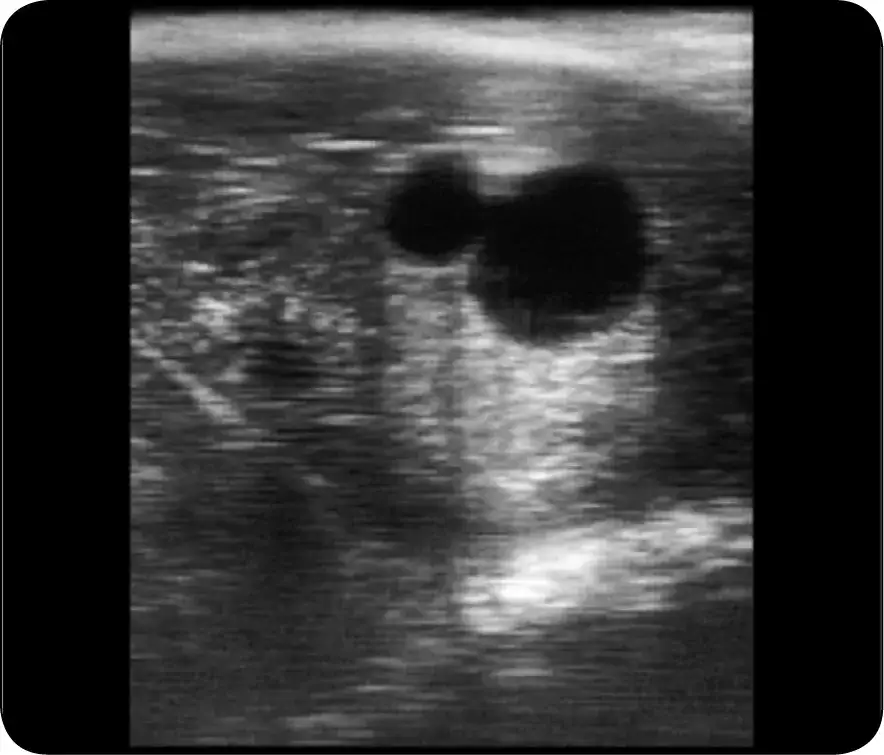

Inną skuteczną metodą jest ultrasonografia, która pozwala na wizualizację zarodka w macicy. To badanie jest szczególnie przydatne w późniejszych etapach ciąży, kiedy zmiany w ciele klaczy stają się bardziej widoczne. Ultrasonografia daje także możliwość oceny zdrowia zarodka, co jest istotne dla planowania dalszej opieki nad klaczą.

- Ultrasonografia: Umożliwia wizualizację zarodka i ocenę jego zdrowia.